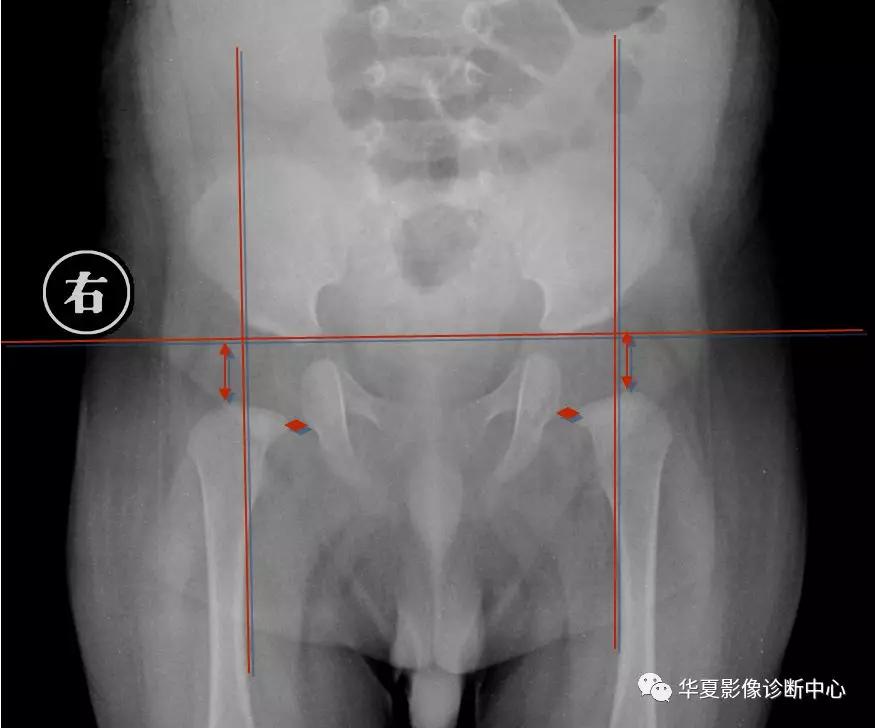

3.Perkin象限

当股骨头骨骺核出现后可利用Perkin象限,即两侧髋臼中心连一直线称为H线,再从髋臼外缘向H线做一垂线(P),将髋关节划分为四个象限,正常股骨头骨骺位于内下象限内。若在外下象限为半脱位,在外上象限为全脱位。

新生儿正常股骨上端鸟嘴状突起位于内下象限内。若在外下象限为半脱位,在外上象限为全脱位。

股骨头预测骨骺法

即以股骨颈上缘为底边,作一等边三角形,三角形顶点为预测股骨头骨骺,再结合Perkin方格法判断。